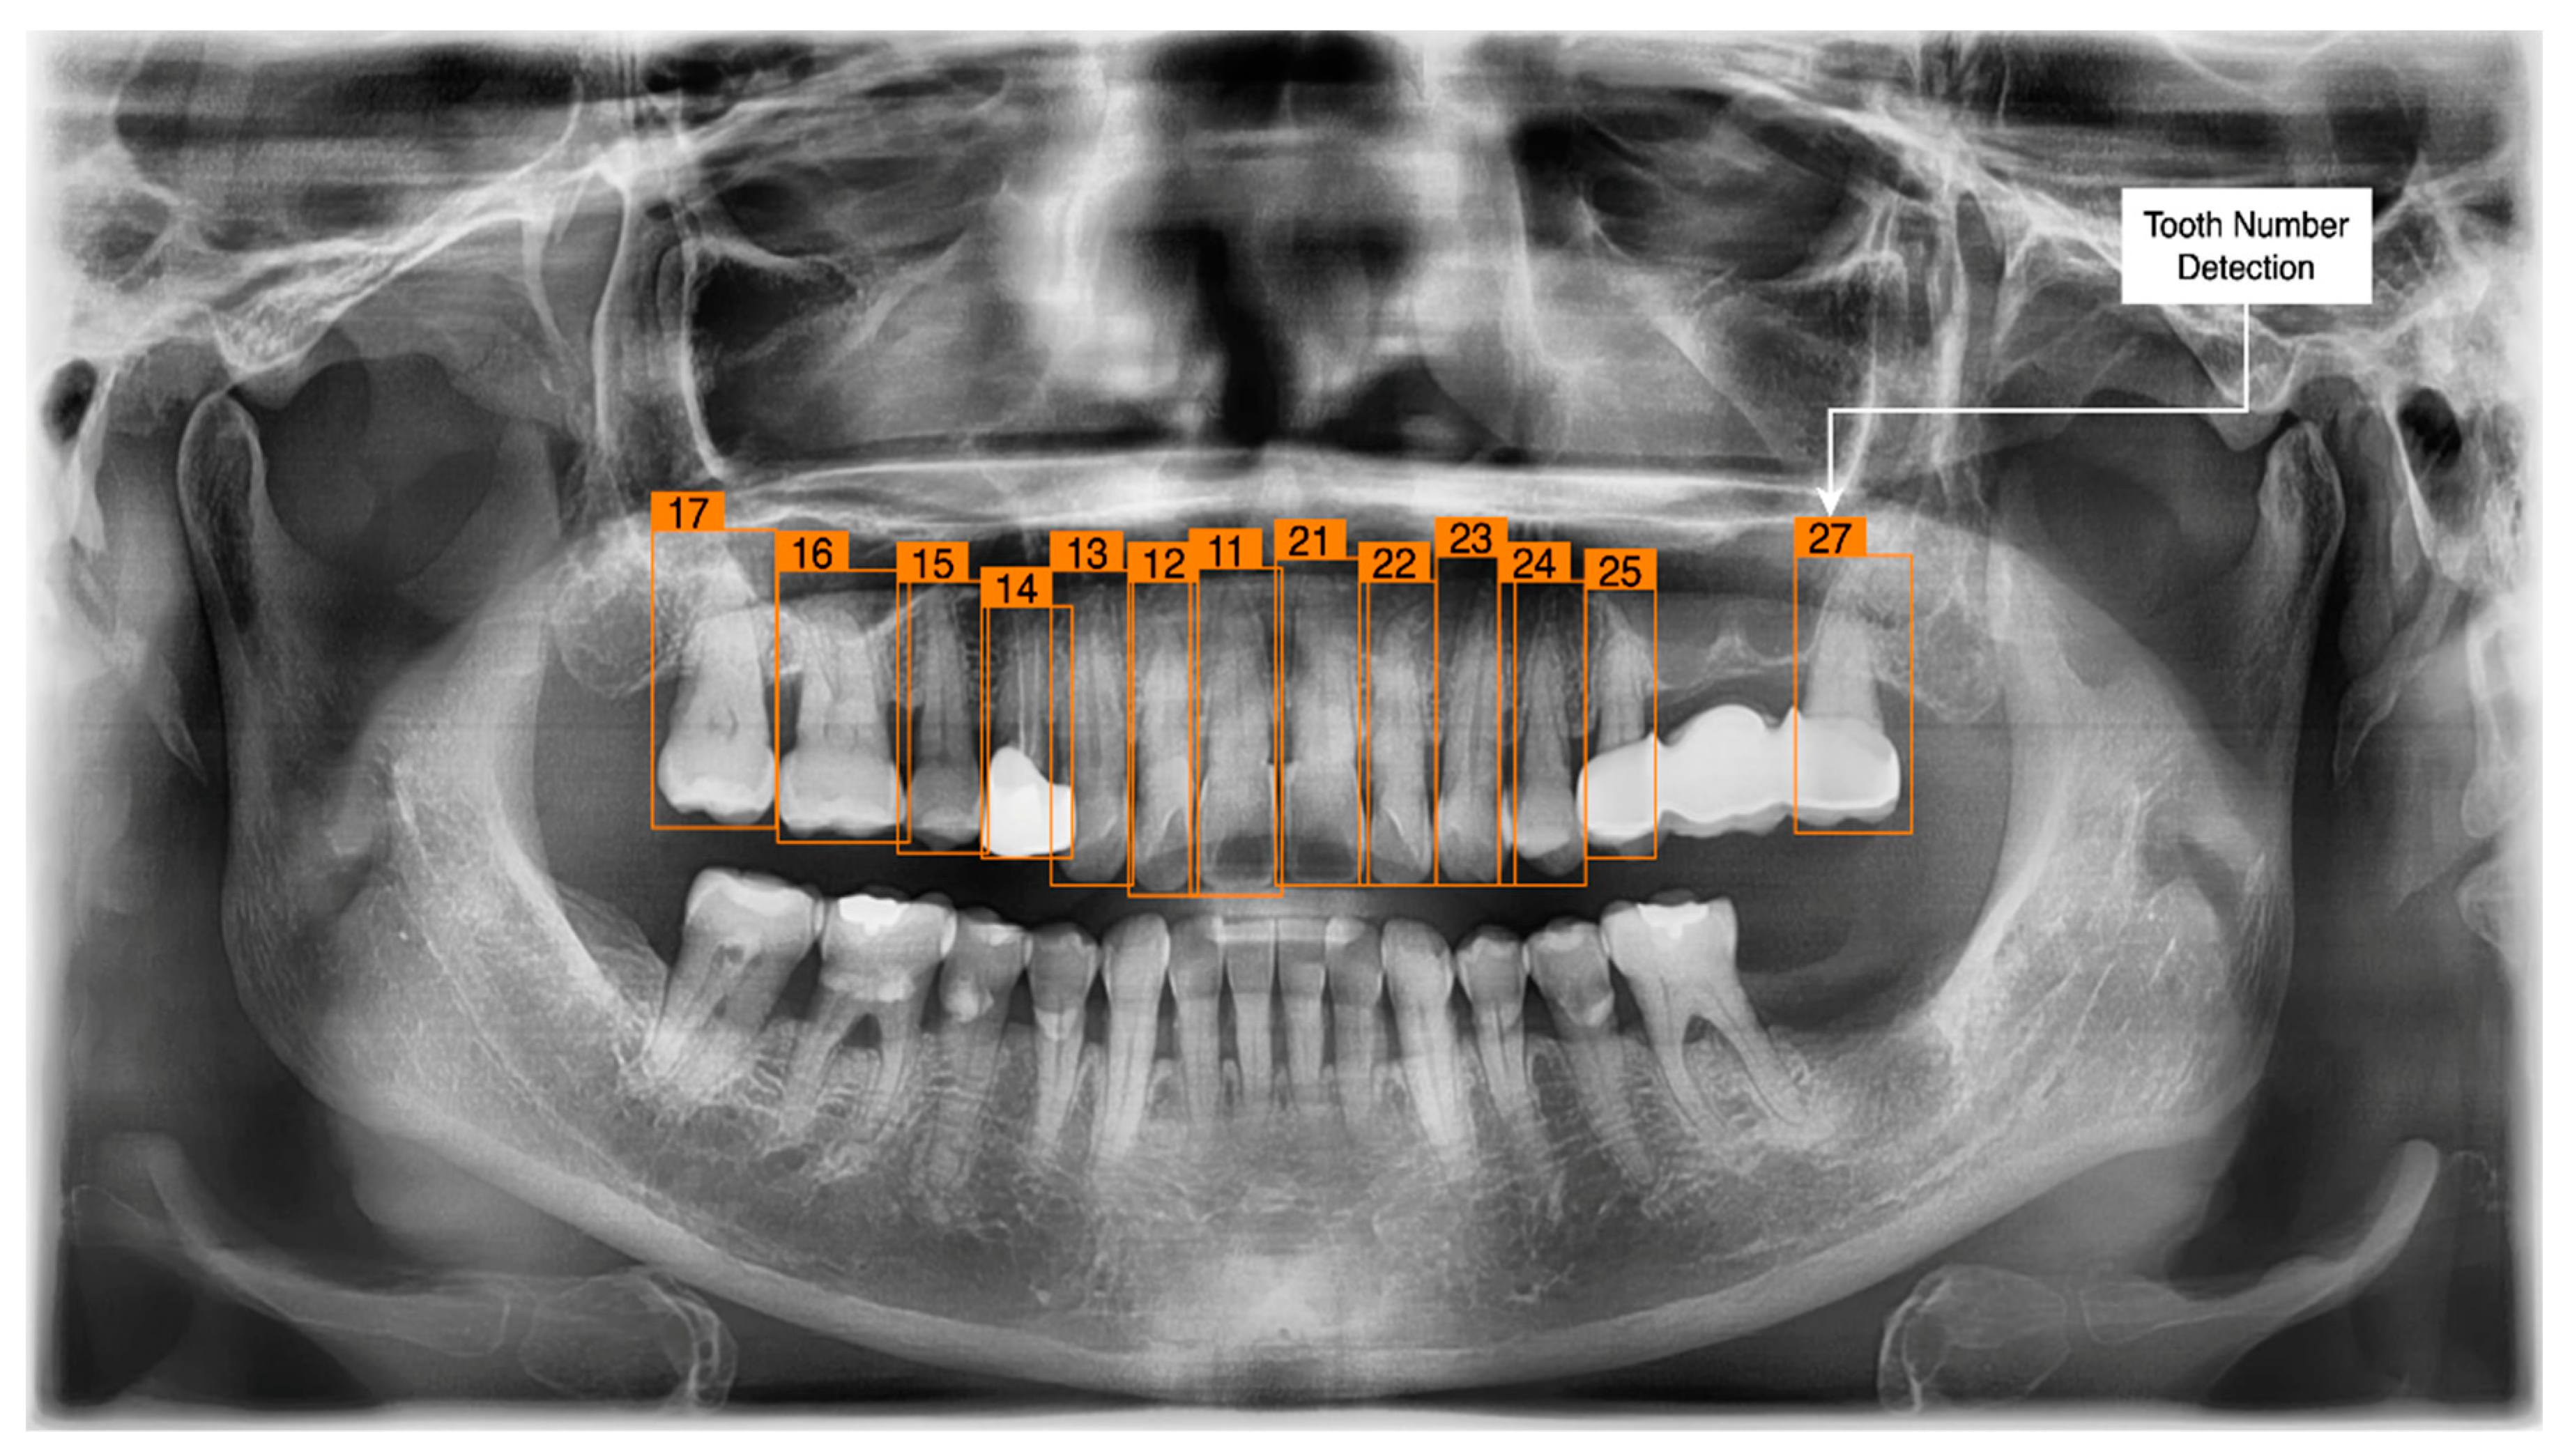

3.3. Tooth Identification through YOLOv5